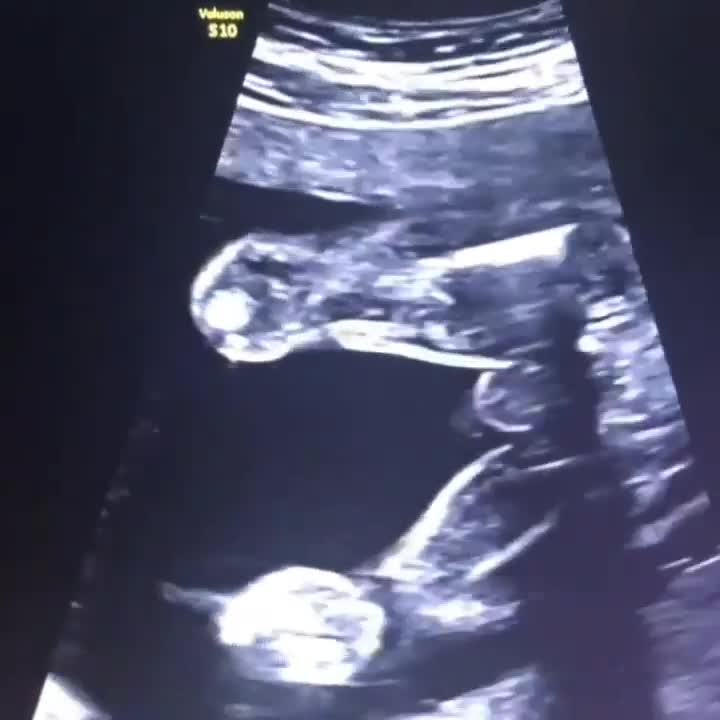

. #هفته_بیستم_بارداری جنین اندازه ی موز😍 پوست انگشتان دست و پای جنین شما از هفته ی نوزده بارداری به شکل مشخصی درآمده است که اکنون دائمی و منحصر به فرد اوست.(اثر انگشت دارد😍) مراکز  بویایی ، چشایی ، شنوایی ، بینایی و لمس در مغز جنین تعیین می شود. دست ها و پاهای او اکنون با یکدیگر و بقیه بدن او متناسب است. یک پوشش محافظ مومی به نام ورنیکس از هفته ی نوزده روی پوست جنین شما تشکیل می شود تا از ترشیدگی آن در مایع آمنیوتیک جلوگیری کند. بسیاری از جوانه های چشایی جنین  شما در هفته ی بیست می توانند سیگنال های چشایی را به مغز او منتقل کنند و مولکول های غذایی را که می خورید و از خون شما به مایعات آمنیوتیک شما رسیده است می بلعد.  برخی تحقیقات نشان می دهد آنچه در دوران بارداری می خورید می تواند روی غذاهایی که کودک شما بعداً ترجیح می دهد تأثیر بگذارد. با رشد رحم ، رباط هایی که آن را به لگن متصل می کنند ، کشیده می شوند و ممکن است باعث درد های گاه به گاه شود. شکم شما در هفته های آینده با سرعت بیشتری رشد می کند. در نتیجه ، ممکن است احساس درد در پایین شکم یا حتی گاهی درد مختصر و تیزی از یک طرف یا هر دو طرف داشته باشید ،به خصوص هنگامی که موقعیت خود را تغییر می دهید یا در پایان یک روز فعال. به احتمال زیاد ، این درد مربوط به رباط گرد است. رباط هایی که از رحم شما در مقابل افزایش وزن و کشش پشتیبانی می کنند. ممکن است کف دستان شما قرمز شود که  به دلیل استروژن اضافی است. همچنین ممکن است لکه هایی  تیره روی لب فوقانی ، گونه ها و پیشانی خود داشته باشید که به آن chloasma یا ماسک بارداری می گویند. رنگدانه های اضافی ممکن است باعث تیرگی نوک پستان، کک و مک ، جای زخم ، زیر بغل ،قسمت داخلی ران و مجرا شود. به خط تیره رنگی که از روی شکم شما به سمت استخوان شرمگاهی شما می رود ، linea nigra یا "خط تاریک" می گویند. به دلیل کشیده شدن پوست برای استقرار جنین در حال رشد ، ممکن است احساس خارش در اطراف شکم و پستان داشته باشید.بعد از مشورت با پزشکتان برای تسکین از مرطوب کننده ها استفاده کنید.